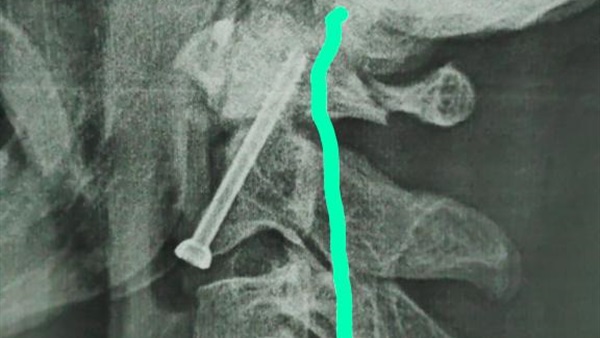

صرح الدكتور مصطفي عبد الخالق القائم بأعمال رئيس جامعة سوهاج ان فريق طبى متخصص من قسم جراحة العظام بالمستشفي الجامعي نجح في اجراء عملية جراحية لتثبيت كسر بالفقرة العنقيه الثانية لشاب في العقد الثلاثين من عمره، وذلك بواسطه التدخل الجراحى من الامام .

وقال "عبد الخالق" ان تلك الجراحة تعد من أكثر جراحات العمود الفقرى خطورة نظرا لقربها من قاع المخ و الحبل الشوكى وتحتاج الي دقة ومهارة عالية في اجراؤها.

واوضح الدكتور حمدي سعد مدير المستشفي الجامعي انه بعد اجراء الفحوصات والاشاعات اللازمة للمريض تبين وجود كسر في الفقرة الثانية من العمود الفقري الرقبي، ويحتاج إلى جراحة عاجلة لتثبيت الفقرة العنقية، حيث كان هذا الكسر يشكل خطراً كبيراً على النخاع الشوكي وحياه المريض.

وذكر الدكتور عبدالرحمن الشيخ رئيس قسم جراحة العظام انه بعد دراسة الحالة في ضوء نتائج الفحوصات الطبية، تم اتخاذ كافة التدابير التحضيرية للعملية، لافتاً الي ان الفريق الطبي الذي إجري العملية الجراحية للمريض كان تحت اشراف الدكتور أحمد صالح أستاذ جراحة العظام والعمود الفقري، حيث تم تثبيت الكسر بنجاح، و بدأ المريض الحركة بحرية تامة بمفرده بدون اي وسائل مساعدة.